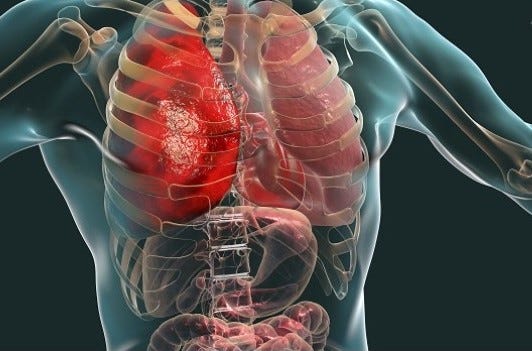

- Organ Damage

Organ damage — organ perforation can occur during many plastic surgery procedures. The equipment used to perform liposuction may especially put patients at risk for organ damage. Deep vein thrombosis — some procedures raise the risk of DVT, which involves the formation of a blood clot in deep veins .